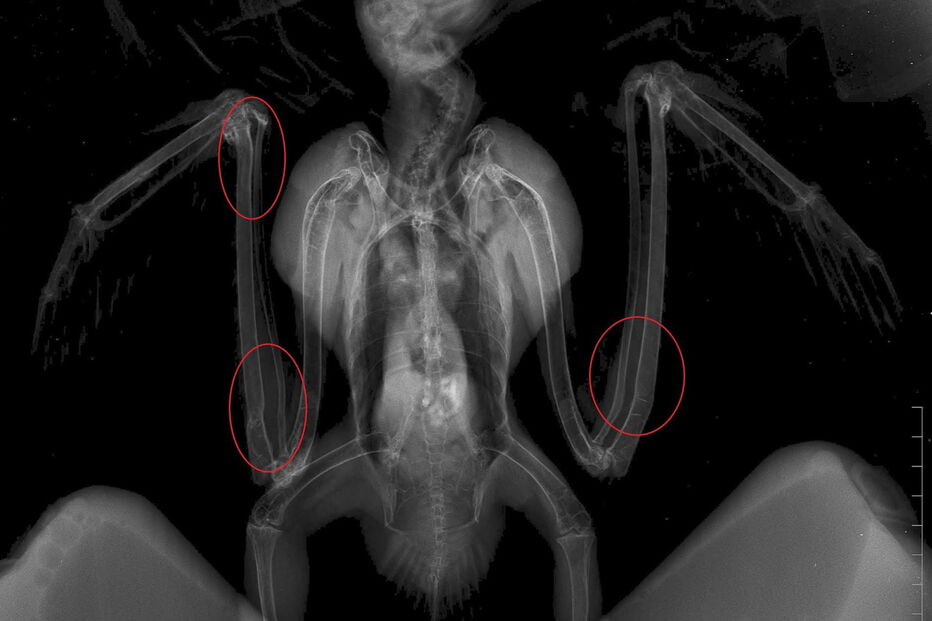

Um milhafre-preto ainda juvenil deu entrada no RIAS - Centro de Recuperação e Investigação de Animais Selvagens, em Olhão, depois de ter sido mantido ilegalmente em cativeiro. Tinha várias deformidades ósseas nas asas e nas patas devido a alimentação inadequada.

“O raio-x mostrou graves deformidades nos ossos, um sintoma compatível com osteodistrofia nutricional, uma patologia frequente em animais com alimentação inadequada durante o crescimento”, refere o RIAS, revelando ainda que “não vai ser possível corrigir estas alterações ósseas.” Ainda assim, a ave, que terá nascido no início deste ano e está no centro desde o final de julho, consegue voar, mas apresenta outro problema: alterações comportamentais que afetam a alimentação.